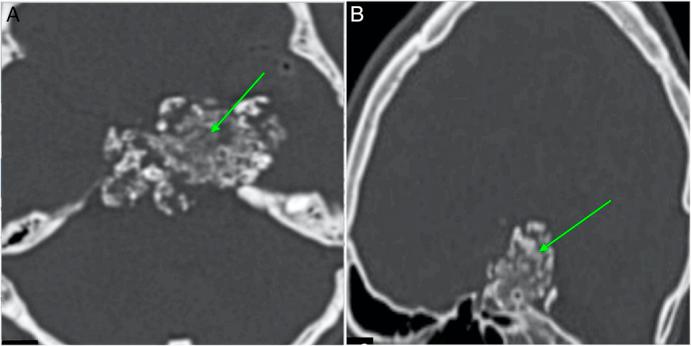

A 34-year-old man with vision deterioration and headaches had an MRI revealing a suprasellar lesion. Intraoperatively, a bony hard tumour was partially resected. Subsequent computed tomography (CT) confirmed a calcified mass contiguous with the posterior clinoid.

一名34岁视力减退且头痛的男性,MRI显示鞍上病变。术中部分切除了一个骨质坚硬的肿瘤。随后的计算机断层扫描(CT)证实有一个与后床突相连的钙化肿块。